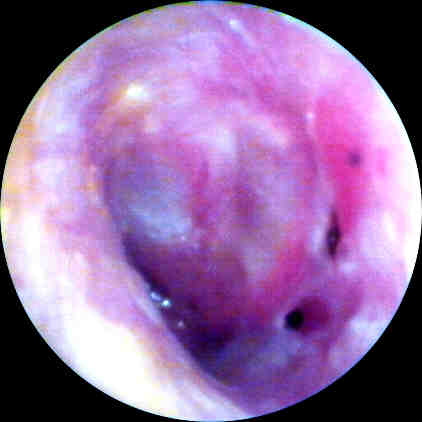

Figure 2. Photo taken in operating room prior to surgery for excision of silicone

impression material from the middle ear cavity. Click image for full size view.

Figure 2 was taken 24 hours after Fig.1, via a surgical microscope using emulsion photography. Some separation of the impression material from the medial surface of the TM is noted.